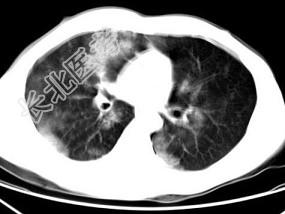

- 单项选择题男,28岁, 外伤后1小时,胸部CT如图, 最可能的诊断为 ( )

A、肺炎

B、肺脓肿

C、肺囊肿

D、肺癌

E、双肺挫伤